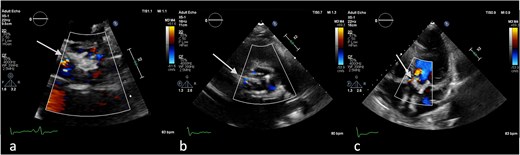

On the third day of hospitalization, transesophageal echocardiography revealed only moderate mitral regurgitation (Videos 3 and 4). However, on day 11, follow-up echocardiography showed a 7 × 18 mm vegetation on the prosthetic aortic valve, with a 5 × 7 mm floating formation (Fig. 2, Videos 5 and 6). By day 21, the vegetation had progressed, with a new formation on the tricuspid valve, an aortic annulus abscess, and worsened mitral regurgitation to severe (Figs 1 and 3, Videos 7 and 8). The development of double-sided endocarditis is very rare, and since the patient experienced it twice, congenital predisposing factors such as Patent Foramen Ovale and ventricular septal defects were ruled out. It was hypothesized that multiple predisposing factors ultimately led to the reinfection. Active IV drug use and its potential immunosuppressive effects, along with persistent poor dental condition and recurrent cutaneous infections, were identified as the main contributors, in addition to the patient’s overall non-adherence, for the development of double-sided endocarditis on two occasions.

(a) Large vegetation on the neo-right coronary cusp of the aortic prosthetic valve in TEE LAX and (b) TEE SAX (day 11 of hospitalization).